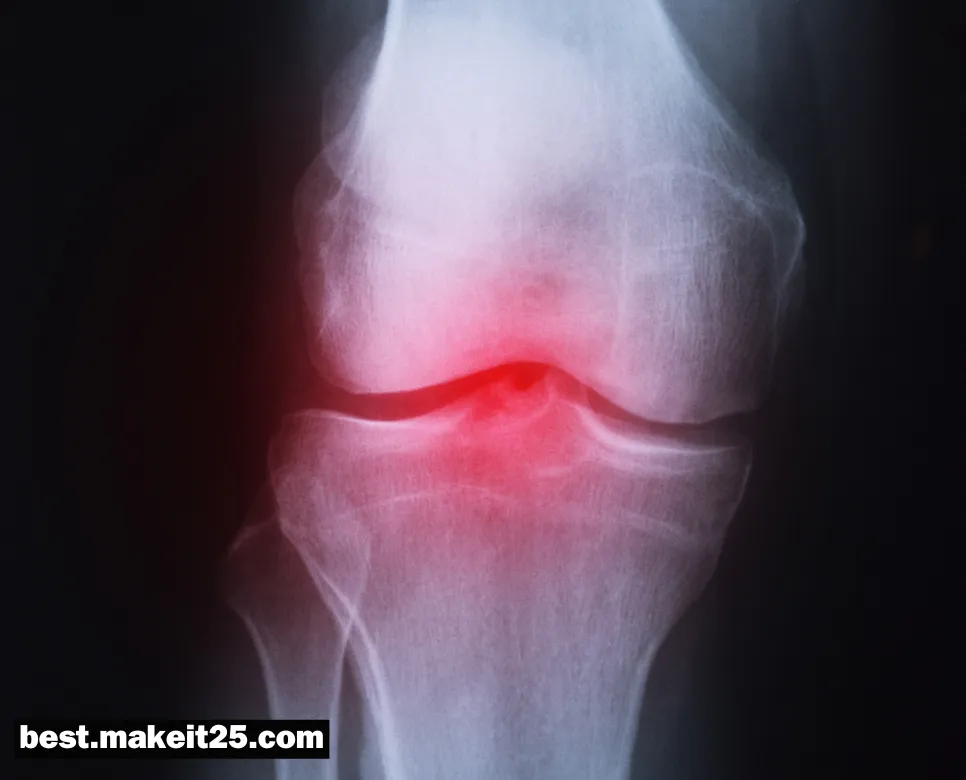

화농성 관절염은 관절 내부에 세균 감염이 발생하여 관절의 염증, 통증, 부종, 발열 등의 증상을 유발하는 질환입니다. 주로 단일 관절에 발생하며, 슬관절, 고관절, 견관절 등의 큰 관절에 호발합니다.

화농성 관절염의 원인

- 세균 감염: Staphylococcus aureus가 가장 흔한 원인균이며, 그 외에도 연쇄상구균, 그람 음성균 등이 원인이 될 수 있습니다.

- 혈행성 전파: 신체의 다른 부위 감염으로부터 혈류를 타고 관절로 전파되는 경우가 많습니다.

- 관절 내 직접 감염: 관절 수술이나 관절 내 주사, 외상 등으로 인해 세균이 직접 관절 내로 침투할 수 있습니다.

화농성 관절염의 진단과 치료

- 관절액 분석과 배양 검사를 통해 원인균을 확인하고 진단합니다.

- 적절한 항생제 치료와 함께 관절액 배농, 관절경 수술 등의 치료가 필요할 수 있습니다.

- 신속한 진단과 치료가 이루어지지 않으면 관절 파괴, 패혈증 등의 심각한 합병증이 발생할 수 있습니다.